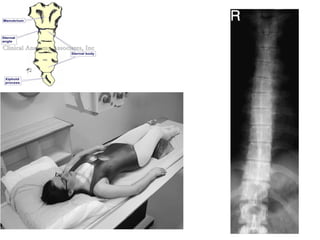

Thoracic Spine

Indications

• Trauma,Fracture,Dislocation,Bone disease,

Inflammation, Degeneration, & Kyphosis,

skoliosis.

Thoracic Spine-Lateral

Position

• Make the patient to lie or stand in front of the x-ray table in

lateral position.

• Mid saggital plane should be parallel to the center of the

table.

• Arm should be raised well above the head.

• The head can be supported by pillow & pads may be placed

between the knee for the patients comfort.

• Radiation Production given to the patient.

Tube Centering

• The tube center at the level of 1" below the axila T7 & T8.

Cassette centering

• The upper border of the cassette is kept 3 to 4 cm above the

spinous process of the C7.

Exposure Settings